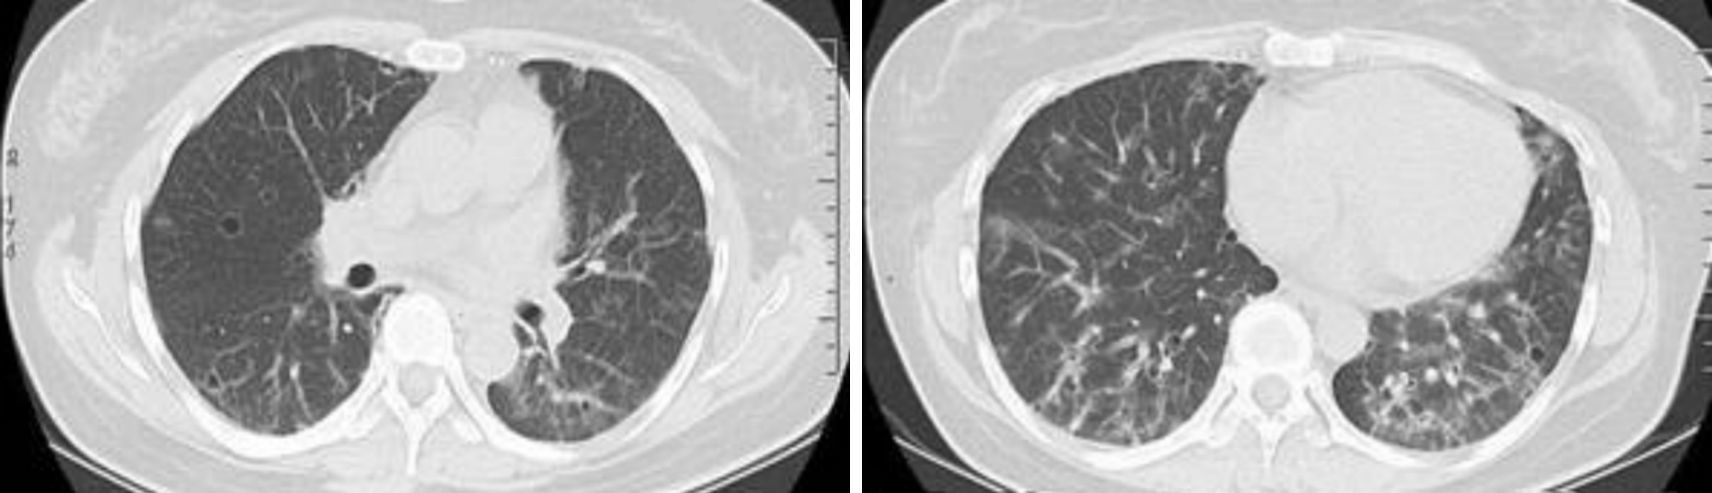

病例2?患者女性,59歲。有過敏性鼻炎、哮喘病史,眼干、口干、鼻干,反復出現腹痛、發熱,兩眼腫脹、左側腮腺及雙側頜下腺腫大,抗SSA抗體弱陽性,血清IgG升高(1 930 mg/dL),未測IgG亞型。行唇腺活檢示大量淋巴漿細胞浸潤,于2006年診斷為“自身免疫性胰腺炎并干燥綜合征”,堅持服用激素及免疫抑制劑,癥狀好轉。2007年出現多飲多尿,渾身乏力,消瘦,經腦核磁共振(MRI)等檢查確診垂體炎。2011年7月出現鼻塞,咳嗽伴胸痛,偶有白色黏痰。胸部CT檢查示雙肺野外帶網格狀及磨玻璃樣密度增高影,左舌葉小葉間隔增厚(圖 4)。給予左氧氟沙星及阿奇霉素無效,遷延10個月余入院治療。實驗室檢查:IgG正常(130 mg/dL),IgG1、IgG2和IgG3均正常,血清IgG4升高(909 mg/dL),IgE升高(323 mg/dL),嗜酸粒細胞增高。抗SSA及抗SSB抗體等自身免疫性抗體均陰性。唇腺病理IgG4陽性漿細胞浸潤,考慮IgG4相關性肺疾病可能性大。給予糖皮質激素后,除垂體炎外,其他癥狀好轉,血清IgG4逐漸減低。臨床診斷為IgG4相關性疾病:間質性肺疾病、米庫利次病、自身免疫性胰腺炎、垂體炎。服用糖皮質激素治療后于2012年 6月7日復查胸部CT,發現與治療前比較右肺磨玻璃影減少或消失,左側舌葉小葉間隔增厚消失(圖 5)。2013年9月復查IgG亞型,IgG1、IgG2和IgG3均正常,IgG4較前減低但仍高于正常(422 mg/dL)。

給予潑尼松40 mg/d口服2個月后無喘息、咳嗽咳痰,測血清IgG為2 200 mg/dL。潑尼松減量為30 mg/d口服1個月后復查血清IgG增高(2 400 mg/dL)。潑尼松繼續減量,同時服用中藥,8個月后停用潑尼松,服用中藥2年。血清IgG控制在1 600~1 700 mg/dL之間。2014年3月26日復查血清IgG稍高(2 090 mg/dL),IgG1稍高(1 250 mg/dL),IgG4正常,CRP、血沉均正常。甲狀腺、乳腺、腹部B超未見異常。胸部CT與之前CT結果比較,發現雙肺磨玻璃影較前明顯吸收,少部分囊泡消失,部分斑片影衍變為小囊泡,小囊泡總量較之前增多(圖 3)。